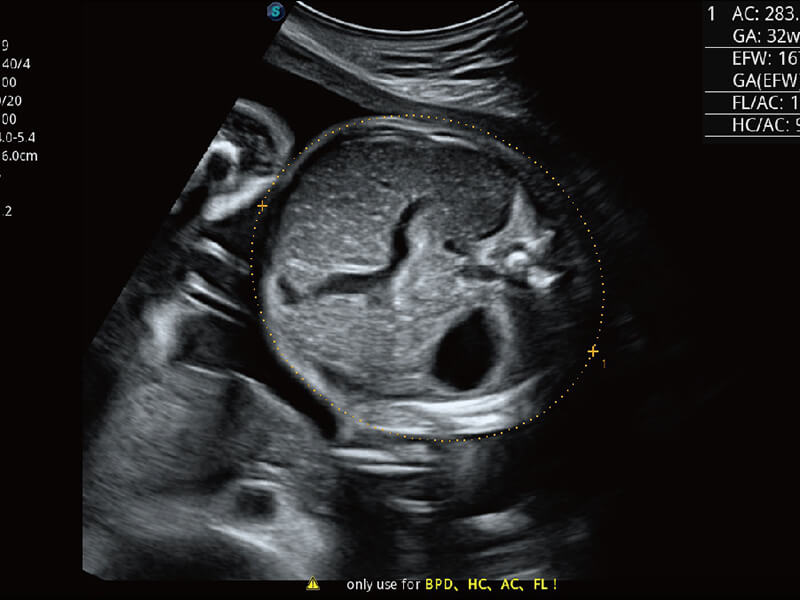

性能优异的硬件架构,极大提升超声系统的运行效率和数据处理能力。相比以往超声成像系统,Wis+平台为您带来极快的响应速度和成像帧频,提升检查流畅度。

S60探头工艺,从前端信号处理每一个环节采集无损声学数据,真实还原组织原貌,再现解剖细节。